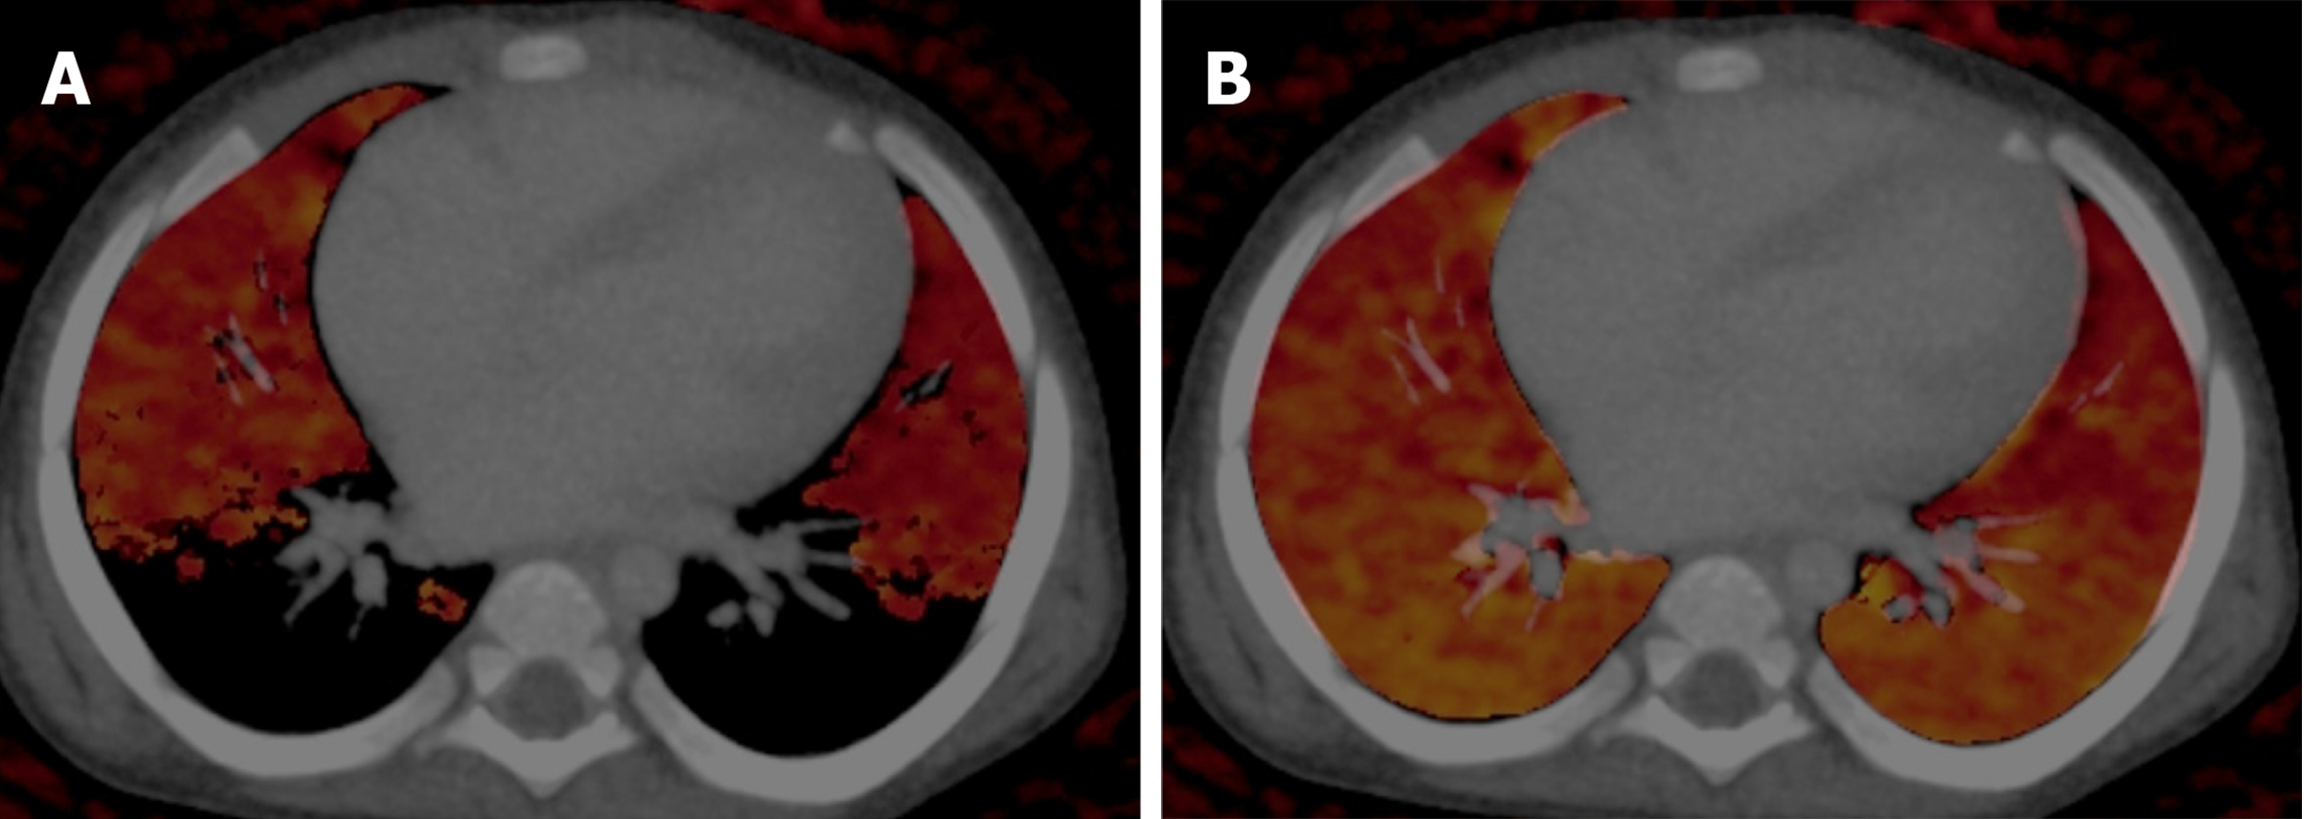

Figure 8 Axial sections of CT pulmonary angiography in a 2-month-old female with infective endocarditis.

A: Complete occlusion of the left pulmonary artery by a thrombus on blended contrast image; B: Complete occlusion of the left pulmonary artery by a thrombus on low kV (80 kV) image, showing increased contrast in the vasculature; C: Lung vessel image showed blue color-coded right pulmonary artery (white arrow) with thrombus being color-coded red in the left pulmonary artery (black arrow), suggesting diminished iodine content; D: Lung blood volume image showed diffusely reduced perfusion in the left lung as compared with the right lung.

Figure 9 Pitfall related to the incorrect CT threshold used for the assessment of lung blood volume.

A: Iodine defects were seen when the maximum threshold was set at -600 Hounsfield units; B: Lung parenchyma showed normal perfusion when the threshold was changed to -300 Hounsfield units. A higher threshold was needed in children to compensate for the higher lung density.